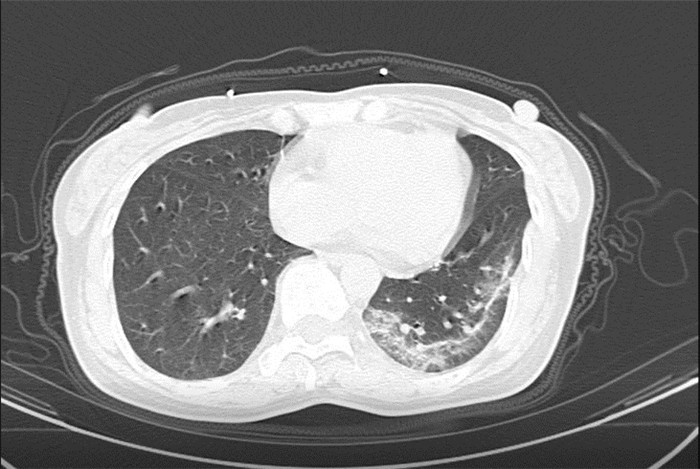

武漢大學(xué)中南醫(yī)院影像科副主任張笑春教授發(fā)現(xiàn),目前武漢市家庭聚集性發(fā)病較多,而且大多起病隱匿,一次甚至多次核酸陰性,無任何臨床癥狀,CT檢查卻已顯示為病毒性肺炎特征。

為了盡快篩查新型冠狀病毒肺炎患者,醫(yī)院會(huì)選擇影像診斷作為早期發(fā)現(xiàn)新型冠狀病毒感染的肺炎的重要一環(huán)。

CT為當(dāng)前首選篩查與診斷的主要影像學(xué)手段,胸部CT的病毒性肺炎檢出率高。

方舟CT(CT Ark)可以滿足全面的臨床功能,配置16層、32層、64層、128層CT,實(shí)現(xiàn)了低劑量掃描要求,配合NDI微劑量迭代技術(shù),智能毫安調(diào)控技術(shù),使各種場(chǎng)合下、各部位低劑量掃描得以實(shí)現(xiàn);超高分辨率CT病灶靶掃描,使病灶的密度顯示更加精確,能夠顯示病灶內(nèi)輕度的密度變化,有利于小病灶的密度定量分析和及時(shí)診斷。